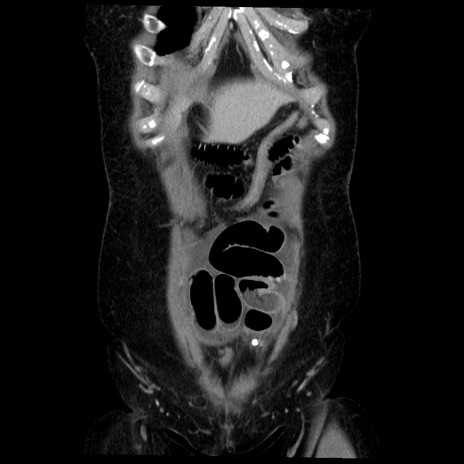

横断像

症例6(冠状断像)

【症例】50歳代女性

【主訴】下腹部痛

【既往歴】卵巣癌術後(8年前に当院で卵巣摘出)

【身体所見】 意識清明、腹部:平坦、腸蠕動音→、やや硬、下腹部自発痛・圧痛あり、反跳痛あり、筋性防御なし。

【データ】WBC 16000、CRP 0.01